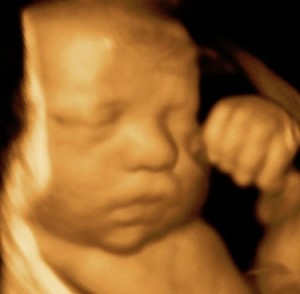

Prenatal Peek®

Prenatal Peek is the leader in 3D 4D Ultrasound. We employ only Certified / Registered Sonographers maintaining unsurpassed standards in 3D ultrasound. You deserve the best! Call us today.